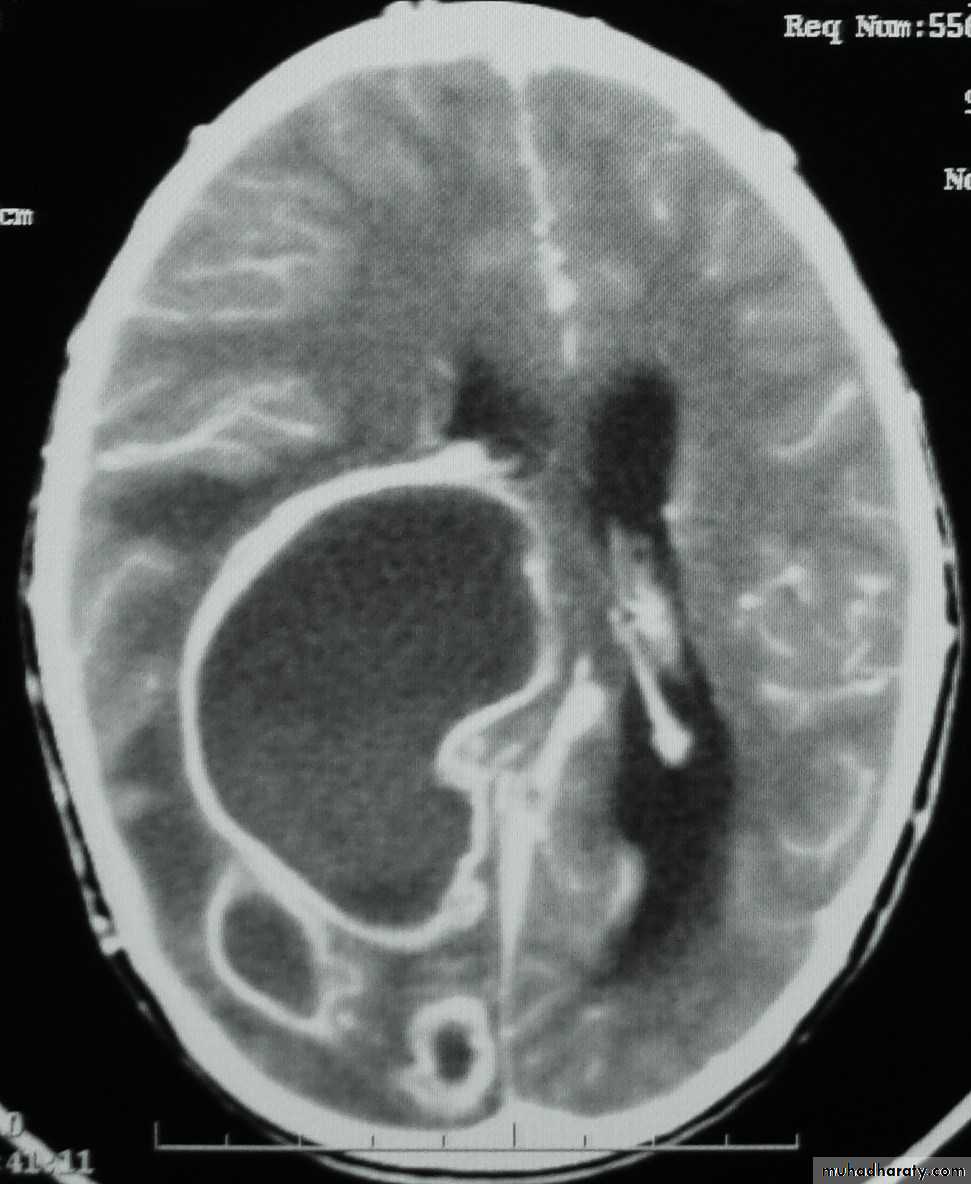

• B. Radiological Investigations:• CT or MRI is the investigation of choice.

• CT Brain is performed with and without contrast.

• MRI is done with gadolinium enhancement.

• They will show a single (or multiple) space occupying lesion that is well delineated with an enhancing wall, with variable surrounding oedema.

Brain Abscess CT without contrast

Brain Abscess CT with contrast

• B. Radiological Investigations:• The differential diagnosis of a single brain abscess in CT or MRI is a solitary metastasis or cerebral infarction.

• The differential diagnosis of multiple brain abscesses is from multiple metastasis and tuberculoma.